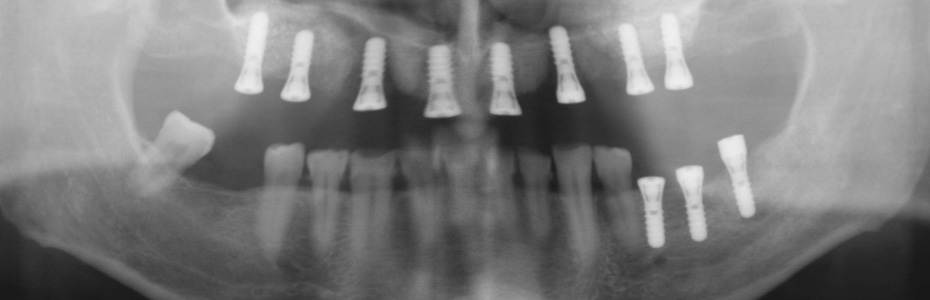

Implantologische Misserfolge

Ein Misserfolg muss nicht immer ein Implantatverlust sein. Auch eine Abweichung von dem mit dem Patienten geplanten und dem erzielbaren Ergebnis kann als Misserfolg verstanden werden.

Vom Misserfolg zur erfolgreichen Behandlung

Unkenntnis oder Versäumnisse

Implantologische Misserfolge können auf Unkenntnis von Begleitumständen und einer ungünstigen Abfolge von Ereignissen oder Versäumnissen beruhen.

Wir zeigen Ihnen an dieser Stelle Patientenfälle, die vorbehandelt in die Praxisklinik für dentale Implantologie gekommen sind und für die wir im Rahmen einer Weiterbehandlung eine Lösung gefunden haben. In vielen Fällen haben wir festgestellt, dass die Misserfolge vorhersehbar und vermeidbar gewesen wären.